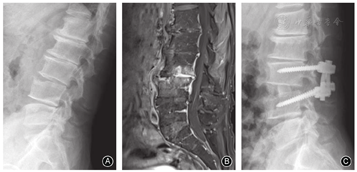

此外,脊柱结核更容易累及多个节段(图1),而化脓性脊柱炎往往局限在2个节段以内。Kim等[7]报告36.2%结核患者受累节段超过3个,而化脓性脊柱炎的比例仅为11.4%,故认为累及3个节段可作为支持结核诊断的重要依据。也有文献报道跳跃病灶现象支持脊柱结核的诊断,但缺乏其他研究的支持[6,9]。

椎体骨破坏是支持脊柱结核的有力证据[13]。结核患者椎体骨破坏比较严重,椎体内形成明显的死骨,因此外科手术时往往选择椎体次全切除进行清创和重建(图4);而化脓性脊柱炎患者的骨破坏往往局限在终板周围,外科手术时更多选择椎间盘连同软骨终板和周围死骨切除清创后,行椎间隙植骨融合(图5)。有学者分析了33例结核和33例化脓性脊柱炎患者,结果显示54.5%化脓性脊柱炎患者椎体无破坏或轻度破坏(<25%),而结核患者椎体破坏几乎是100%;仅6%化脓性患者椎体破坏>75%,而结核患者比例高达45.4%[9]。所有结核患者均存在椎体骨皮质破坏或丢失,而仅39.3%化脓性脊柱炎存在骨皮质破坏[9,14]。

出现后凸畸形也是支持脊柱结核诊断的证据。回顾我们的病例资料,脊柱结核患者出现后凸畸形的原因,除了好发的胸椎本身存在生理性后凸外,椎体骨破坏导致的塌陷是最主要因素;而化脓性患者骨破坏较轻,因此很少出现明显的后凸畸形[9]。文献报道结核患者后凸角度明显大于化脓性脊柱炎患者[15]。